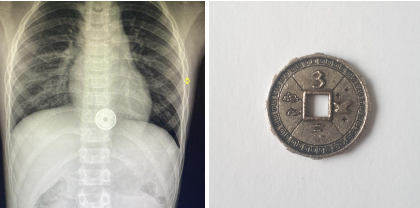

Врачи больницы скорой медпомощи (БСМП) №2 провели успешную операцию по извлечению пластиковой монеты с металлическим напылением из пищевода 8-летнего мальчика. Этот случай стал уже вторым за месяц, когда медики сталкиваются с подобной проблемой у детей.

По информации медицинского учреждения, операция прошла успешно, и мальчику уже оказана необходимая постоперационная помощь. Врачи отмечают, что случаи, когда дети проглатывают мелкие предметы, к сожалению, не редкость. Это особенно актуально для детей младшего возраста, которые могут не осознавать опасности, связанных с такими действиями.